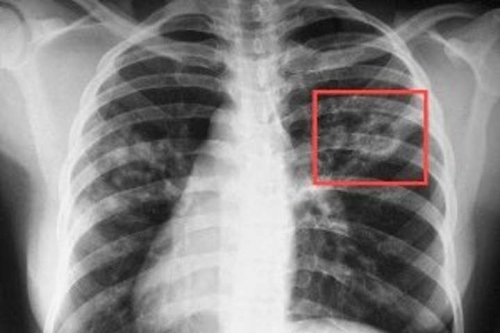

В социальной сети житель Запорожской области распространил информацию о смерти школьника от опасной болезни — туберкулеза

Пользователь социальной сети рассказал, что мальчик болел в течение двух лет, в настоящее время посещая школу. После смерти ребенка, заболевание в закрытой форме диагностировали у еще одного ученика ООШ №3 в городе Каменка-Днепровская.